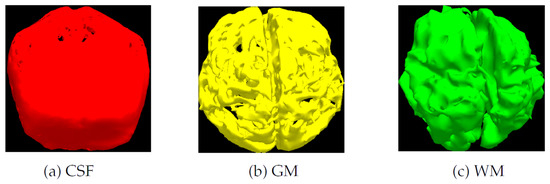

Segmentation Results